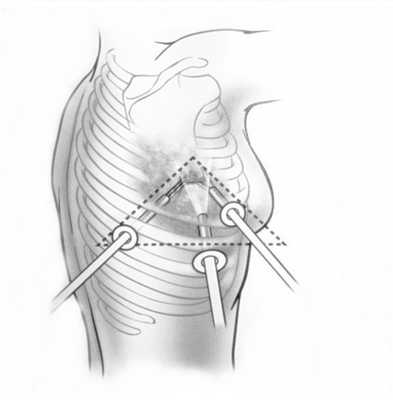

В первичном обследовании пациента, страдающего раком легкого, должны принимать участие несколько специалистов: опытный рентгенолог, специалист по ядерной медицине (радионуклидным методам — сцинтиграфии и ПЭТ), рентгенохирург (специалист в области интервенционной радиологии), пульмонолог, торакальный хирург; необходимо также использовать точные и экономически эффективные методы диагностики. Существующие на данный момент руководства содержат рекомендации, что методы нужно выполнять любому пациенту, у которого имеется высокий риск рака, предпочтительно с выполнением гистологического исследования и взятием образцов ткани. Это позволяет не только установить точный гистологический вариант опухоли, но и правильно стадировать заболевание. Во многих случаях предпочтительнее выполнить биопсию подозрительных лимфоузлов средостения, а не первичной опухоли, что позволяет лучше оценить стадию (например, при биопсии лимофузла с выполнением ПЭТ ставится стадия T2N2, в то время как без ее использования - T2Nx). Кроме того, для опухолей, осложненных обструктивной пневмонией, и образований с выраженными некротическими изменениями, данные играют важную роль для определения области биопсии.

Опухоль левого легкого с частичным некрозом и деструкцией ребер. Визуализируются два метастаза в подключичных лимфоузлах и в мышцах (стрелки), которые на КТ не видны. Необходимо выполнить трансторакальную биопсию той части опухоли, которая расположена в периферических отделах, чтобы получить образец жизнеспособных тканей.

При невозможности получить образец ткани для исследования эндоскопически применяются инвазивные методы: трансторакальная биопсия, медиастиноскопия, видеоторакосокпия. Последние два метода — это серьезные операции, которые проводятся в специализированных медицинских учреждениях.